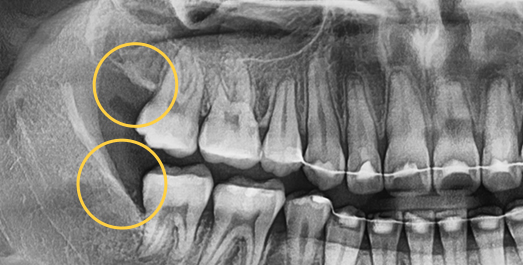

• 수직으로

숨어있는 사랑니

• BEFORE

• AFTER

치료기간 : 2024.05.28